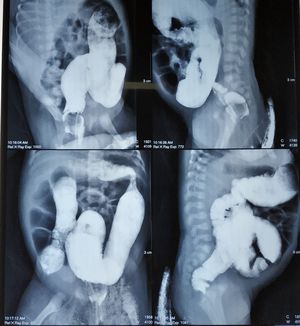

What you can find?

Surgical

Pediatric

Digestive

Volvulus

Hisprung disease?

A megacolon

Volvulus .....

Sigmoidal volvulus